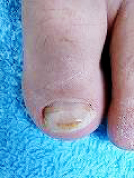

巻き爪、タコ、魚の目等があると症例に示すように、様々な症状を呈します。

早いうちに処置をして快適な生活を心がけましょう。